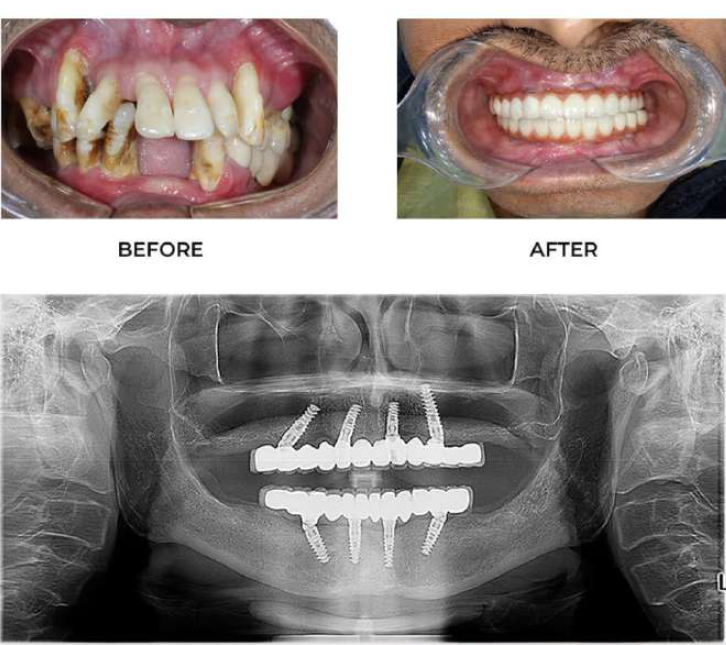

✅ Step 1: Consultation & Evaluation

Digital X-rays and oral examination.

✅ Step 2: Implant Placement

Titanium implant is placed into the jawbone.

✅ Step 3: Healing (Osseointegration)

Implant fuses with bone over few months.

✅ Step 4: Crown Placement

Custom-made tooth crown is fixed.

At Dr. Wadkar’s Dental Clinic, we specialize in replacing missing teeth with solutions that look, feel, and function exactly like natural teeth. Using the latest Digital Implant Workflow, we ensure every procedure is minimally invasive and highly predictable.

2. Full Mouth Rehabilitation

For patients with significant tooth loss, we offer comprehensive full-arch restorations. Utilizing techniques learned from masters, we stabilize your entire smile with a few strategically placed implants.

● The Benefit: Eat what you want, speak clearly, and look years younger with a stable, permanent smile.